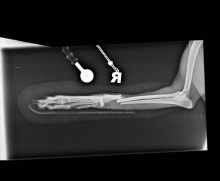

Pantarsal arthrodesis in a Dog

Pantarsal arthrodesis in a Greyhound dog using a dorsal plate for the treatment of a highly comminuted fracture of the ...